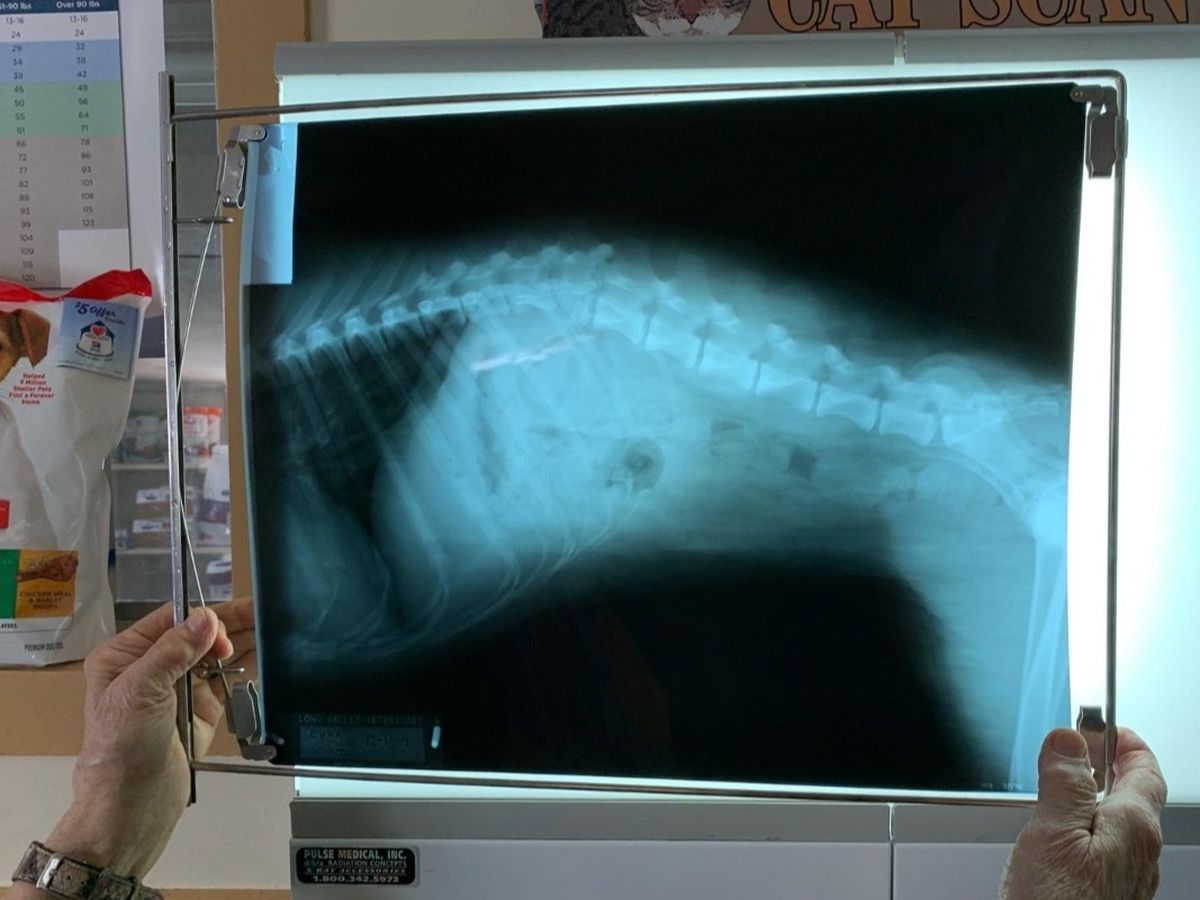

I am raising money so I can afford to get my dog Luna back surgery. We were recently in a pretty serious car accident and Luna damaged a vertebrae. She isn't completely paralyzed but the swelling on her spinal cord is preventing her from controlling her back legs and she is in an extreme amount of pain. I don't want my dog to suffer and if she doesn't get surgery her recovery could be much longer and more painful, if she recovers at all. My next best option is to put her to sleep but I am willing to try whatever I can to help my girl. I'm not usually one to ask for help but I'm not able to afford the surgery at this time. Luna is only 8 months and I really want to give her another chance to live a good life. Anything helps